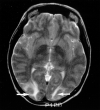

fig. 2. T2-weighted MR image (2500/84/2) obtained on the day of presentation shows typical areas of subcortical white matter abnormality without cortical involvement (arrows) in patient (case 2) who was conditioned for transplantation with cyclophosphamide and TBI and who presented with confusion and altered mental status 14 d after transplantation. She did not develop seizures. At the time of toxic reaction, she had grade 4 BMT-related TM and a CsA level within the normal therapeutic range. Her baseline blood pressure of 115/85 mm Hg increased to 167/104 mm Hg at the time of toxic reaction and MR imaging